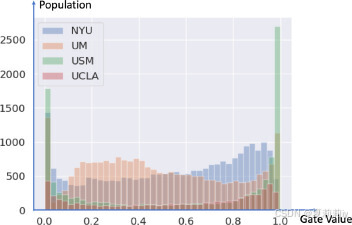

(2)MoE Gating value

①Gate value in different sites:

(gate value是learnable的参数)(哥们儿怎么在画图啊不能化成三维吗后面的都被挡住了)